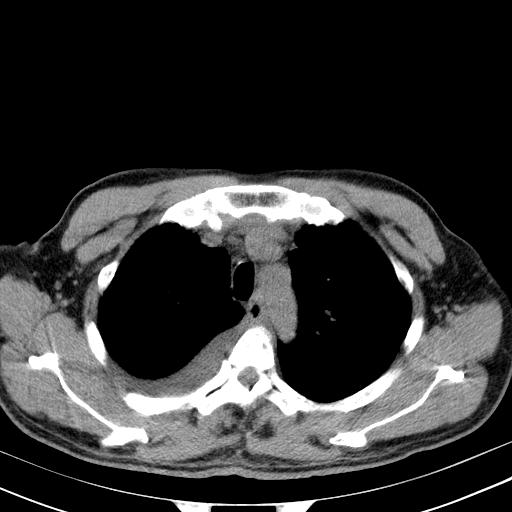

以下是引用zjzjr在2010-3-21 17:39:00的发言:[br]右下中心型肺癌并阻塞性肺炎/不张,纵膈淋巴结肿大,右侧大量胸腔积液,左侧少量胸腔积液

以下是引用zxl51642在2010-3-21 17:06:00的发言:[br]右下中心型肺癌并阻塞性肺炎/不张,纵膈淋巴结肿大,右侧大量胸腔积液,左侧少量胸腔积液,少量腹水。建议纤维支气管镜进一步检查。